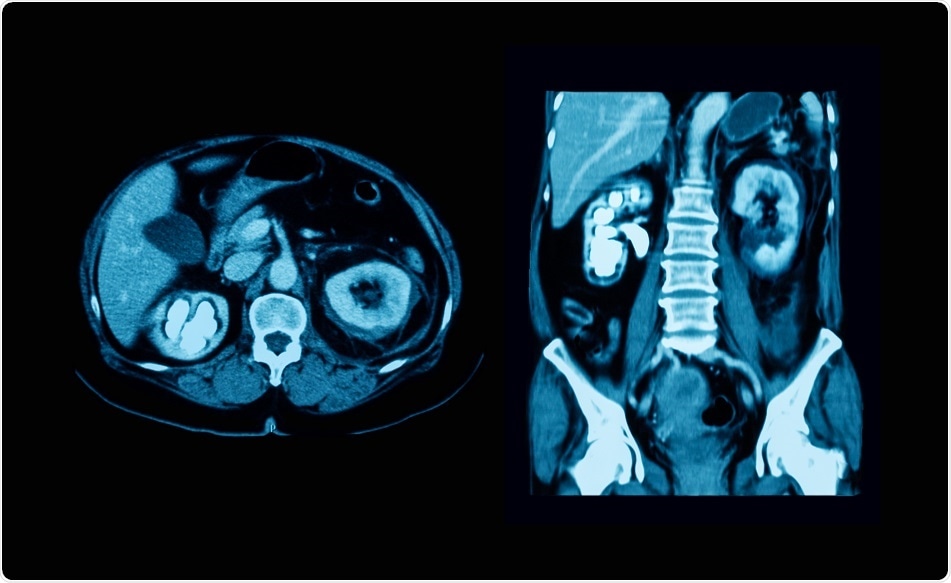

Credit: Suttha Burawonk/ Shutterstock.com

Although a computed tomography (CT) scan of the abdominopelvic region may be the imaging modality of choice for some, there are cases where ultrasound sonography of the urinary tract or radiographic images with or without contrast may be preferable. In addition to imaging tests, urinalysis and blood work may be ordered.

Plain urological radiography of the abdomen is also referred to as a kidney-ureter-bladder (KUB) radiograph or a flat plate. This imaging modality yields accurate results which help to locate the stone as well as its shape, size and composition. With regard to the latter, cysteine and uric acid calculi are radiolucent, whereas calcium stones are radiopaque. A further advantage of the KUB radiograph is that it is relatively quick to perform and inexpensive.

In contrast to the KUB radiograph, a CT scan is more expensive and exposes the patient to much higher doses of radiation. Moreover, smaller stones are difficult to see with CT scans and these scans may not identify some radiolucent calculi. To escape these disadvantages, the CT scan may be combined with KUB radiograph, based on many recommendations.

Nonetheless, the CT scan is an excellent imaging modality to help rule out more sinister pathologies, like abdominal aortic aneurysm, and, like the KUB radiograph, it can be used to determine the properties of the stone. This latter advantage is crucial for planning therapy.